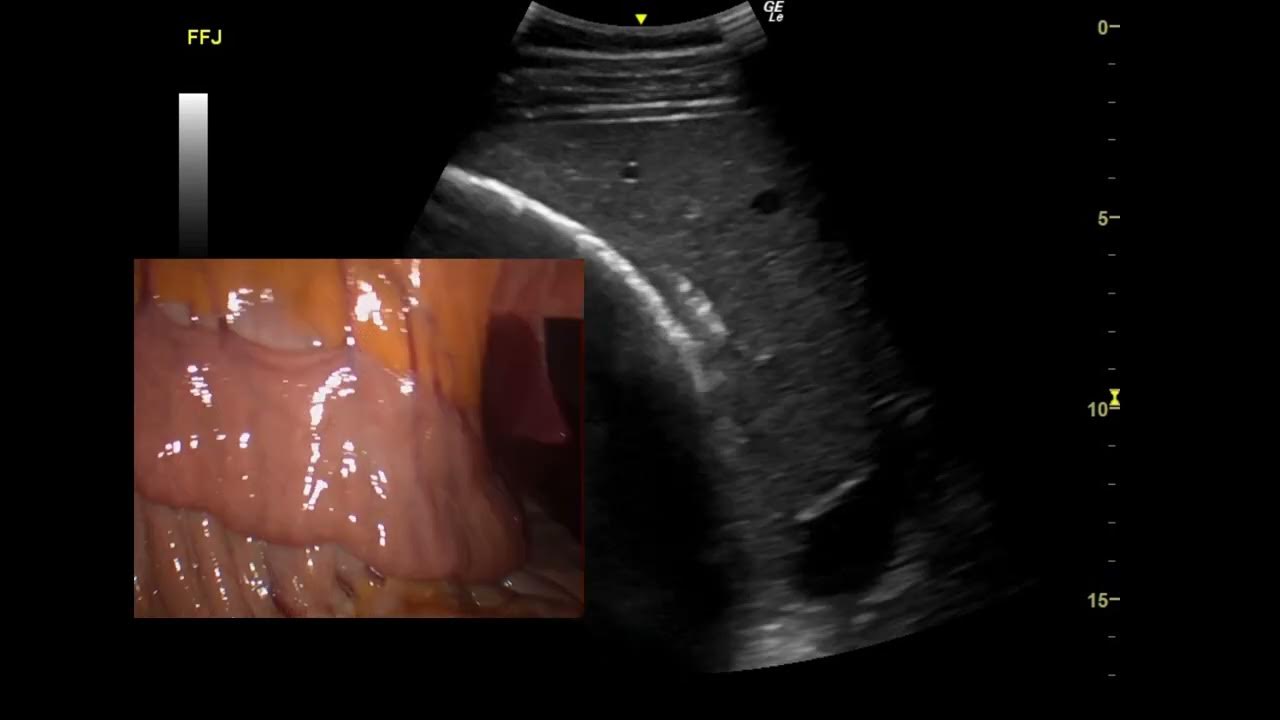

From www.youtube.com

Equine Ultrasonography of Duodenum YouTube Duodenum In Horse The next part of the horse's digestive tract is the small intestine. the horse’s digestive system has two parts: to exit the stomach, digesta/ingesta flows through the pyloric sphincter, into the first portion of the small intestine, the. the duodenum is the start of the small intestine and is around one metre long. the duodenum is. Duodenum In Horse.

Equine Colic Ultrasound Distended Duodenum YouTube Duodenum In Horse the duodenum is the start of the small intestine and is around one metre long. Approximately 70 feet in length, it is made up of. to exit the stomach, digesta/ingesta flows through the pyloric sphincter, into the first portion of the small intestine, the. the duodenum is short, approximately 1 m, and can be separated into a. Duodenum In Horse.

From www.researchgate.net

Sonogram of the duodenum (D) at the right 16 th ICS in an Arabian... Download Scientific Diagram Duodenum In Horse The duodenum starts the si and is approximately one metre long. to exit the stomach, digesta/ingesta flows through the pyloric sphincter, into the first portion of the small intestine, the. Digestion of proteins, fats and hydrolyzable carbohydrates (such as those found in grain) takes place mainly in the foregut. the duodenum is the start of the small intestine. Duodenum In Horse.

1(a, b) Ultrasonogram of ascending duodenum (Horse) at 12 th ICS. The... Download Scientific Duodenum In Horse Digestion of proteins, fats and hydrolyzable carbohydrates (such as those found in grain) takes place mainly in the foregut. Bile is also secreted direct from the liver, as the horse has no gall bladder to store it. The foregut consists of the mouth, esophagus, stomach, and small intestine. The foregut and the hindgut. The duodenum starts the si and is. Duodenum In Horse.